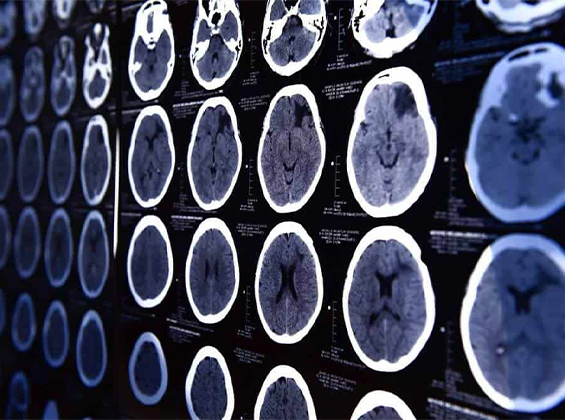

Advanced Neurological Diagnostic & Treatment Facilities

At Kartik Oraon Multispecialty Hospital, we use state-of-the-art diagnostic tools to accurately assess and treat neurological disorders. Our advanced neurology lab and imaging center include:

🔹 CT Scan & MRI Brain: For detecting strokes, tumors, and neurodegenerative conditions.